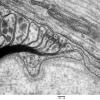

PERIPHERAL NEUROPATHY

3 NORMAL MYELIN & SCHWANN CELLS

2 Node of Ranvier (2)